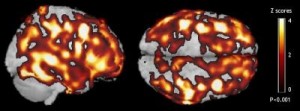

Brain Composite Image 1: Two views of a composite image of the brains analyzed in Dr. Mosconi's study highlight the average increase in amyloid-beta deposits among 14 healthy adults with a mother affected by Alzheimer's. Regions in yellow have 4 times more amyloid than the corresponding regions of 14 healthy counterparts with no family history of dementia, while regions in red have twice as much amyloid. (Credit: Lisa Mosconi, Ph.D., Mony J. de Leon, Ed.D.)

The study examined 42 healthy individuals, including 14 whose mothers had Alzheimer’s, 14 whose fathers had Alzheimer’s, and 14 counterparts with no family history of the disease. On average, the first group of volunteers showed a 15 percent higher burden of amyloid-beta deposits than those with a paternal family history, and a 20 percent higher burden of the protein clumps than those with no familial risk factors.